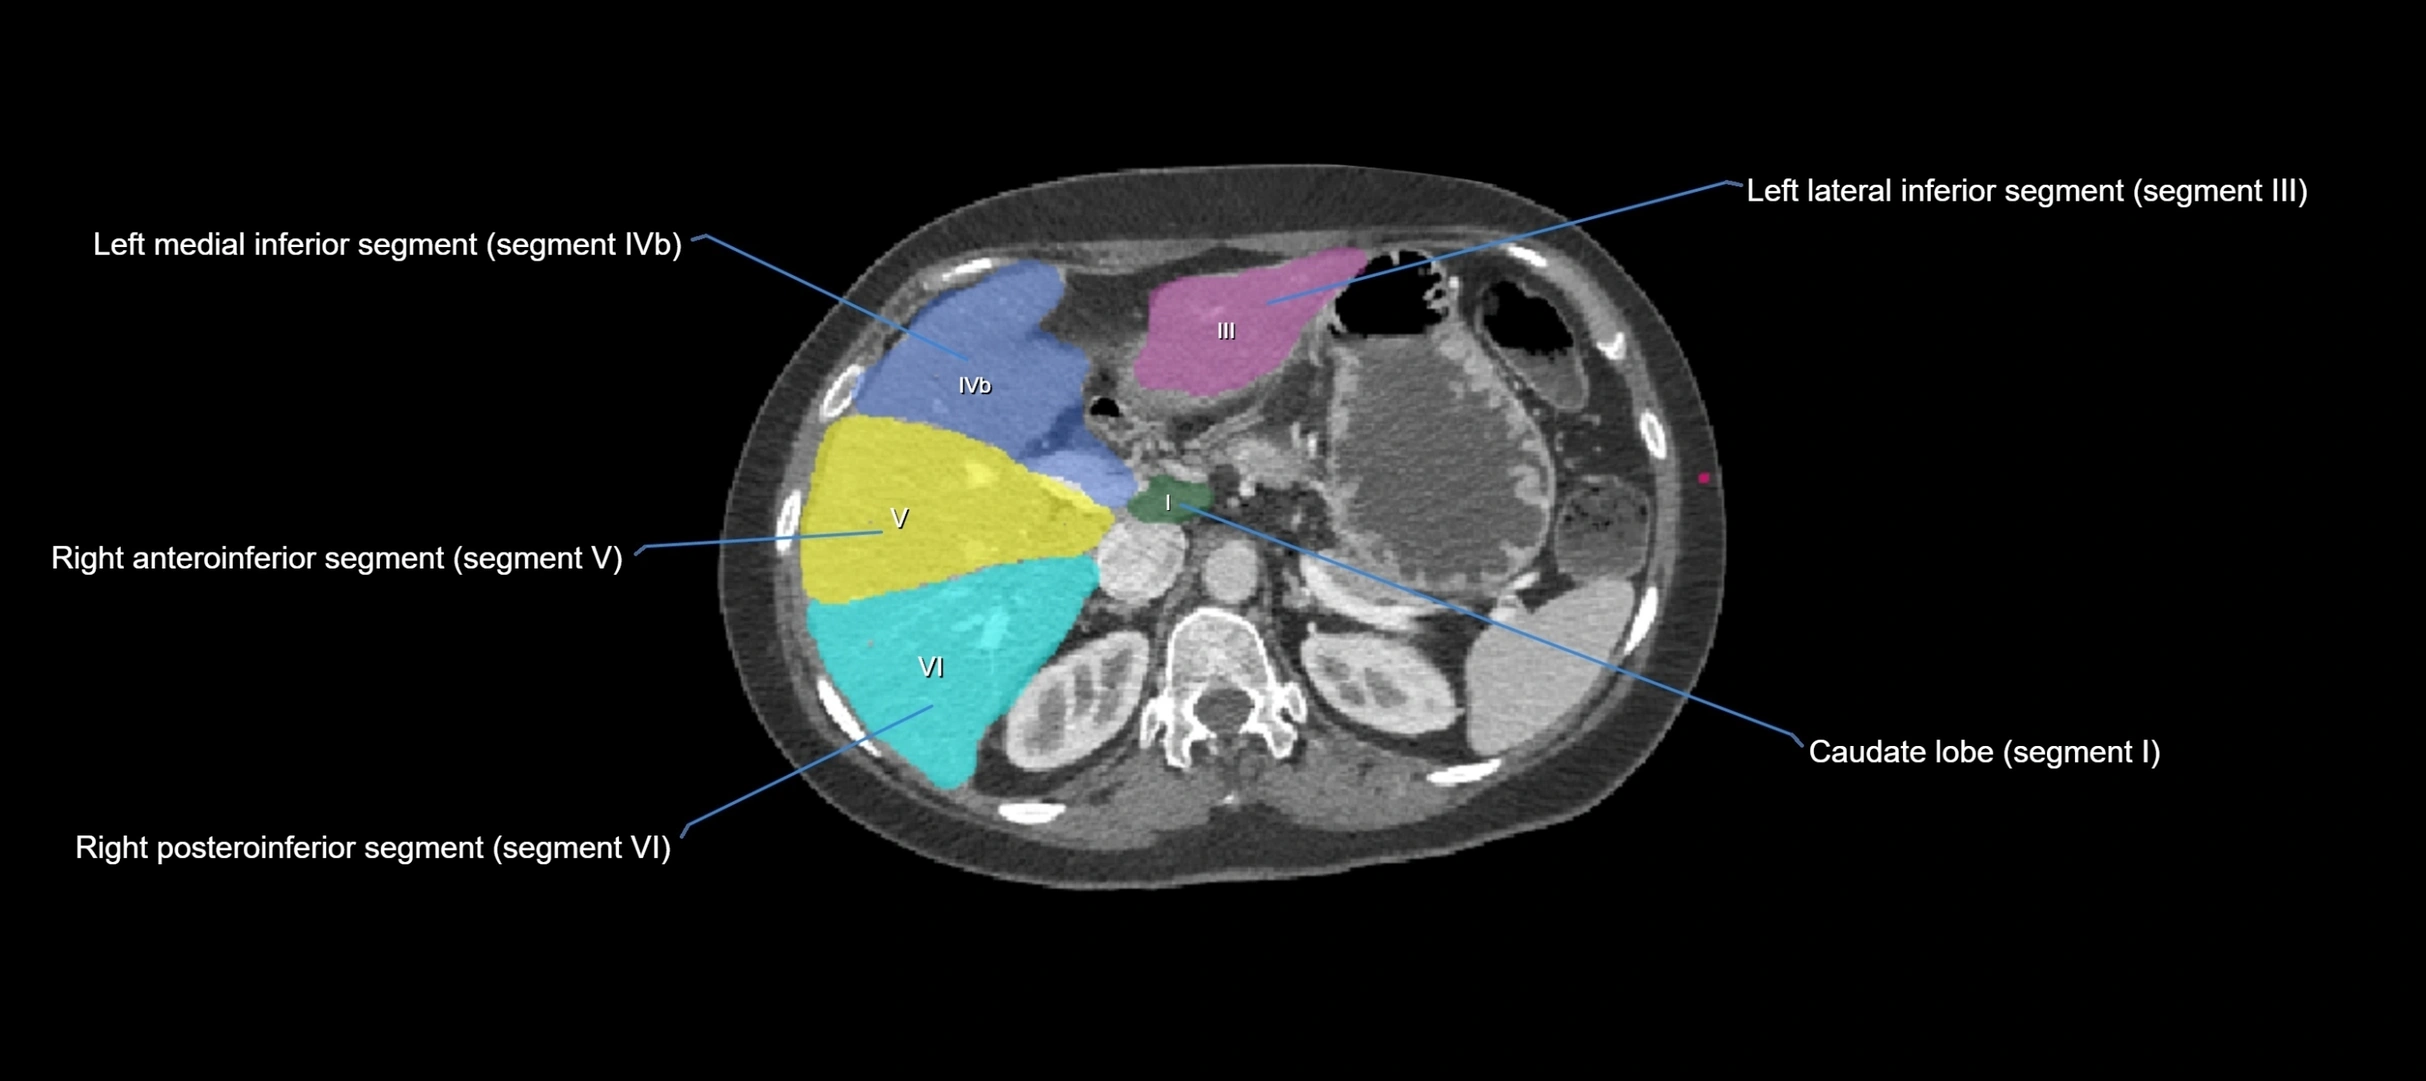

CT Image

image